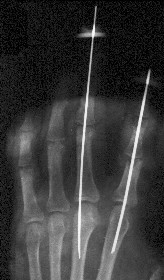

Уважаемые коллеги, в травмотделение БСМП Ангарска поступил пациент с отрывом 3 пальца на уровне проксимального межфалангового сустава (дистальная

часть пальца висит на кожном лоскуте с латеральной стороны пальца шириной 1 см, повреждены сухожилия сгибателей и разгибателей), многооскольчатым переломом головки основной фаланги 2 пальца, рваной раной в проекции сустава, превышающей половину диаметра пальца (сухожилия целы)(снимок 1, снимок 2). Выполнена ПХО ран, МОС спицами трансартикулярно (снимок 3, снимок 4). При обсуждении тактики лечения возникли разногласия между врачом, выполнявшим ПХО, и заведующим. Зав. отделением считает, что выбранная тактика неверна, и необходимо было после проведения ПХО сделать вытяжение типа Черкес-Заде за пальцы. Просим высказать присутствующих свое мнение о выполненной операции и о дальнейшей тактике лечение больного. Заранее спасибо.